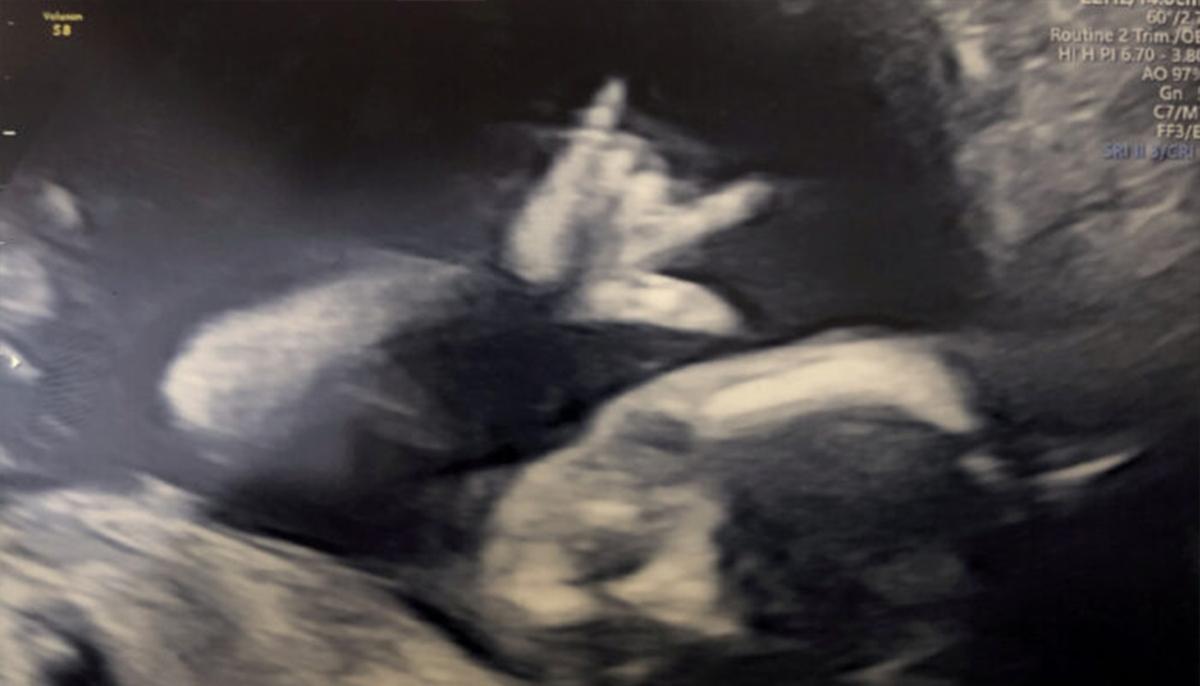

A rock fan dad was given a surprise performance after his unborn baby was seen making a heavy-metal sign in the womb during a baby scan.

Tom Dowie, 29, and fiancée Caitlin Welsh, 28, were at their week-19 scan on Nov. 2, 2019, when their unborn baby gave them the “sign of the horns.” The cheeky baby appeared to be holding up its index and little finger while holding its other fingers—looking exactly like the heavy metal rock sign.